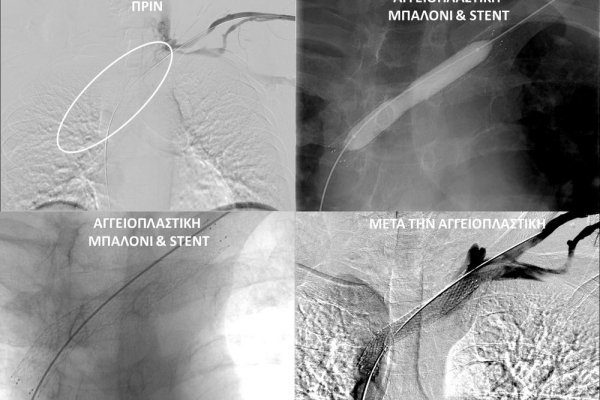

- Φιστουλογραφία ονομάζεται η αγγειογραφία των μοσχευμάτων-fistula αιμοκάθαρσης. Είναι είναι μια ελάχιστα επεμβατική διαγνωστική εξέταση που ενδείκνυται για την ανάδειξη στενώσεων που θέτουν σε κίνδυνο την λειτουργία της αγγειακής πρόσβασης και δεν επιτρέπουν την επαρκή αιμοκάθαρση. Η εξέταση διενεργείται με τη χρήση αγγειογράφου και ιωδιούχου σκιαγραφικού μέσου.

- Η φιστουλοπλαστική είναι μια ελάχιστα επεμβατική μέθοδος αντιμετώπισης της δυσλειτουργίας των αρτηριοφλεβικών προσβάσεων αιμοκάθαρσης (μοσχευμάτων ή fistula) λόγω αρτηριακών ή φλεβικών στενώσεων, χωρίς να χρειαστεί χειρουργείο. Η φιστουλοπλαστική διενεργείται σε αγγειογραφική σουίτα με συνθήκες αποστείρωσης και υπό τοπική αναισθησία, ενώ η θεραπεία περιλαμβάνει συνήθως την διαστολή της αγγειακής στένωσης με ειδικό «μπαλονάκι» υψηλών πιέσεων. Στη περιπτωση όπου οι αγγειακές διαστολές δεν επιφέρουν το επιθυμητό αποτέλεσμα, τοποθετούνται μεταλλικές ενδοπροθέσεις (stents).